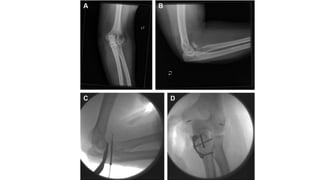

•The coronoid can frequently be approached through the

lateral approach, because the radial-sided structures are

commonly already interrupted.

•If suture fixation is chosen 2 drill holes are created along

the subcutaneous border of the ulna to serve as tunnels

for the suture, directed toward either side of the

coronoid footprint

•Typically the coronoid fragment is too small to

accommodate drill holes and, therefore, is most

commonly captured by passing a number-1 braided

suture through its anterior capsular attachment

•The coronoid canfrequently be approached through the lateral approach, because the radial-sided structures are commonly already interrupted. •If suture fixation is chosen 2 drill holes are created along the subcutaneous border of the ulna to serve as tunnels for the suture, directed toward either side of the coronoid footprint •Typically the coronoid fragment is too small to accommodate drill holes and, therefore, is most commonly captured by passing a number-1 braided suture through its anterior capsular attachment